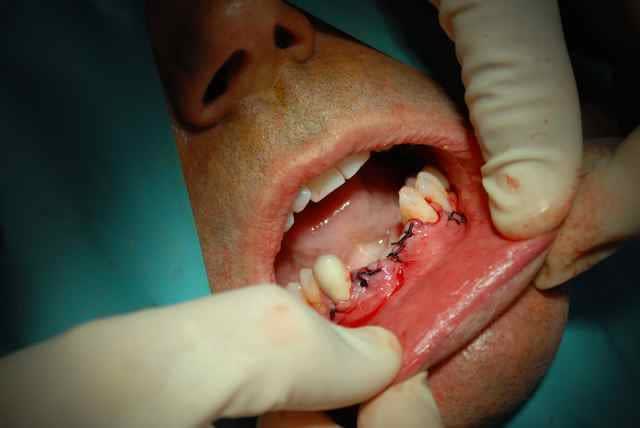

bonjour, ce cas d expansion est superbe, on peut pas toujours et cette situation clinique avec une crete hyperfine +concavite juste en dessous mais plus de nonosse plus bas m a fait preferer une petite greffe classique, facile puisque une seule zone deonneuse receveuse.les implants prevus dans 5 mois.

pour suturer pas de problemes de plans -le lambeau part du sulcus des dents et dans ce cas precis au milieu de la crete edentee. pour les prelevements symphysaires je suis les conseils des "anciens" et je prefere sauf contre indications faire une incision niveau sulcus ; c est a peine plus long pour le decollement mais les fibres musculaires sont dans le lambeau et jusqu a present peu de suites post op.

le repositionnement du lambeau est simple et qq sutures simples suffisent.

les complications que j'ai rencontrees sont essentiellement au niveau des sites receveurs a la mandibule avec des petites expositions tardives au niveau des vis . au niveau du ramus , plutot de l' oedeme post op essentiellement mais des greffons plus longs et essentiellement du cortical donc interessant au maxillaire en apposition, une meilleure acceptation du site pour le patient qui peut faire l analogie avec une dds.